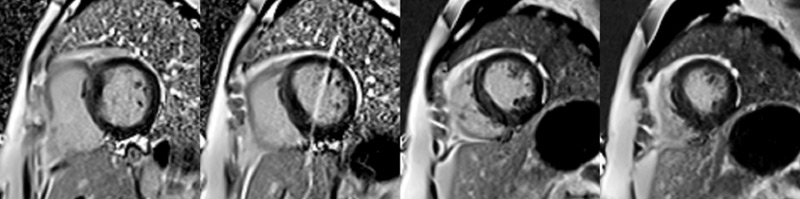

Figure 2 : Séquence T1-mapping pré-injection, coupes petit-axe

Figure 3 : Séquence de Réhaussement tardif

Coupes petit-axe

Figure 4 : Séquence de Réhaussement tardif

Coupes long-axe 4 cavités et 2 cavités

Bonus pour aller plus loin : savoir identifier des artéfacts de mouvement

Présence d’un artéfact de mouvement lié à la respiration (bande blanche signalée par les flèches jaunes) visible au niveau de la 2e image des coupes petit-axe en PSIR. Cet artéfact est appelé « ghosting » ou « image fantôme » et correspond à un dédoublement du signal de la paroi thoracique du patient.